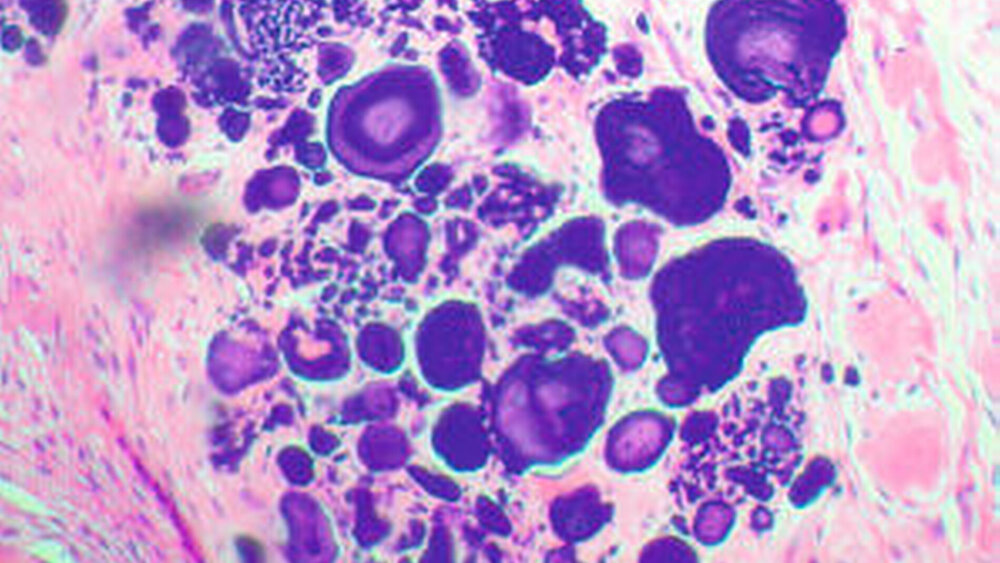

In Lokalanästhesie wurde in der Folge eine Gewebebiopsie entnommen. Die histologische Untersuchung wies polyedrische Epithelzellen, dicht in fibröses Weichgewebe verpackt, nach. Zwischen den Zellinseln fand sich homogenes, eosinophiles, amyloid-ähnliches Material. Eine folgende Kongorot-Spezialfärbung konnte das Vorliegen von Amyloid bestätigen (Abbildung 5).

Weiterhin ließ sich in der Probe eine ausgeprägte, ringförmige Kalzifizierung (Abbildung 6) nachweisen. Diese Ergebnisse, zusammen mit der klinischen Untersuchung, wiesen auf einen kalzifizierenden epithelialen odontogenen Tumor hin. Daher wurde die Läsion in Vollnarkose mit Sicherheitsabstand in toto exzidiert.